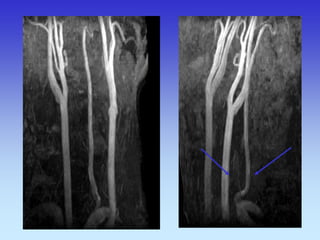

METODE PRIKAZA KRVNIH ŽILA

•UZ-DOPPLER

•DSA

•CTA

•MRA